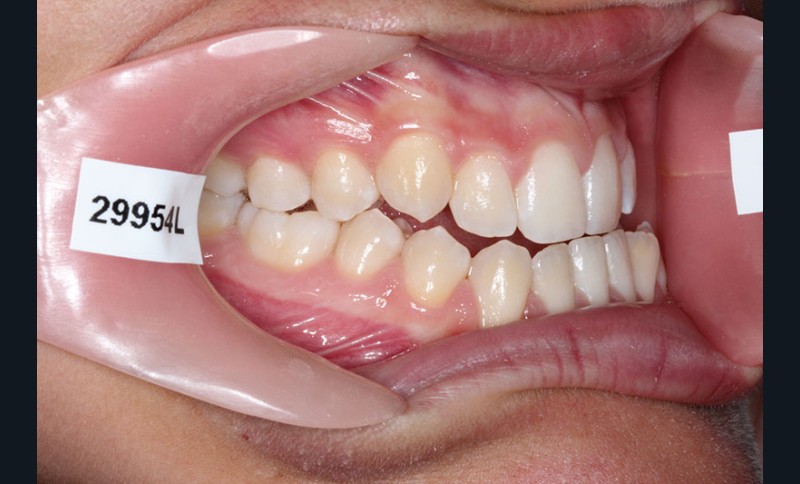

Cas clinique n° 2 : Motion Classe III

Nous sommes en présence d’une patiente en fin de croissance faciale, âgée de 16 ans. Elle présente une classe III dentaire et squelettique associée à une asymétrie faciale de type latérognathie mandibulaire avec déviation des points interincisifs et déviation du menton vers la gauche.

1re phase : recul des secteurs latéraux mandibulaires avec le Motion Classe III Carriere (fig. 4 à 6)

Nous mettons en place des bras latéraux Motion associés à des élastiques intermaxillaires ancrés sur des brackets sur 17 et 27 et une gouttière thermoformée maxillaire portée jour et nuit :